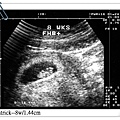

Patrick 八週時,身高1.44公分